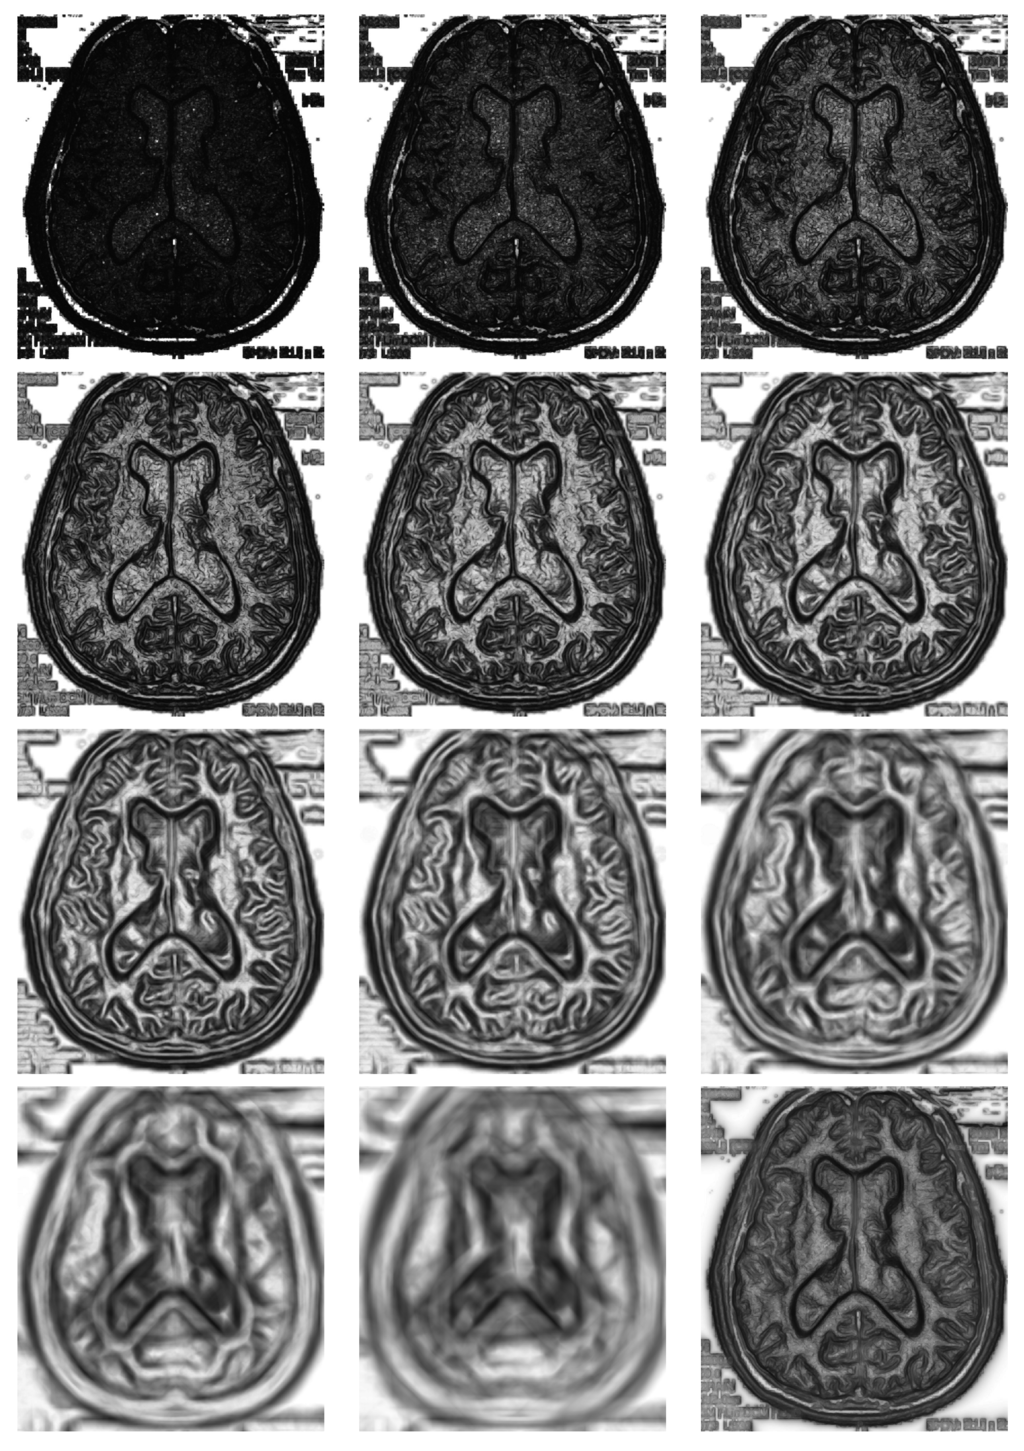

The use of a double sliding window clearly implies that some choices must be done by the user, namely the shape and the size. With respect to the shape, we have decided to use at all times a round window divided into two semicircles. This is the most unbiased decision with respect to all directions. Obviously, all this has to be adapted to the discrete array of pixels in a digital image. However, the size cannot be setup independently of the image. This is a factor bound to the particular image at hand, the size of the objects and the resolution. In Figure 4, we show the matrix of divergences for several radii { 2 , 3 , 4 , 6 , 8 , 11 , 16 , 23 , 32 , 45 , 64 } distributed as a rounded geometric progression of a ratio of 2 ; the corresponding images show good and bad choices of the radius. The choice of a size that is too small can give something like the first image on the top at the left, where many divergences are very high, thus saturated, and objects will be hardly detected, because they are hidden among many unimportant details. Conversely, a size that is too big, apart from the high computation time, can lead us to something like the image at the right at the bottom, cleaner, but where edges appear very blurred and a little out of place.

It may be that choosing a particular radius could be adequate for a particular image. If we do not know what is the range of sizes of the objects to be detected in the image at hand, then it is advisable to use several window sizes at the same time and, finally, combining them in a convenient way. To do this, we chose a set of different radii and take for each image pixel the mean of the divergences, as is shown in the last figure on the bottom in Figure 4.

In right bottom image of Figure 4 is shown the average divergence matrix corresponding to eleven different radii from two to 64 in a geometric progression. Depending on what we need, this last could be more adequate than a particular radius to obtain a good segmentation, as described in the next section. In addition, this choice makes the general procedure more independent of the double window size, since the problem of adjusting the radius is automated. Figure 5 shows the variation of maximum and mean divergence in the matrix for the experiment of Figure 4 (Brain), depending on the radius.

Figure 4. In this figure, we compute divergence matrices for radii of { 2 , 3 , 4 , 6 , 8 , 11 , 16 , 23 , 32 , 45 , 64 } , respectively from top to down, left to right. In the last picture, we used multi-size window.